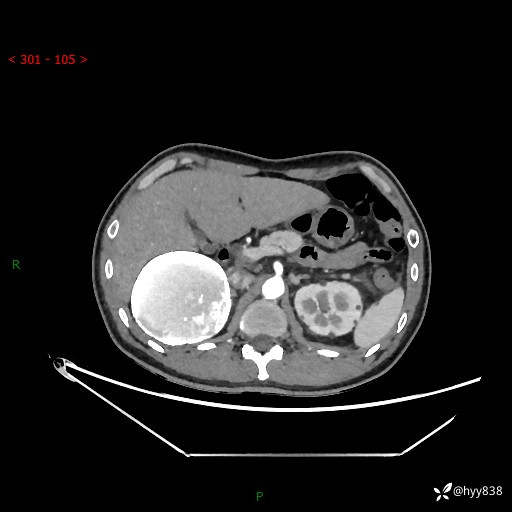

性别:男

年龄:50岁

简要病史:夜尿增多半月,发现肾功能异常1天,超声发现腹膜后占位

腹部CT平扫+增强

增强